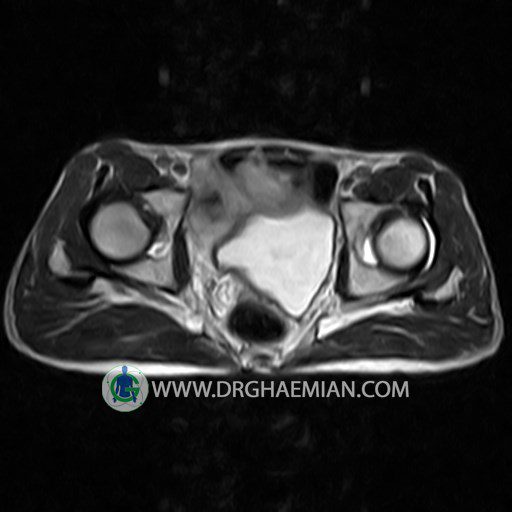

پزشکان اغلب از تصویربرداری ام آر آی برای تشخیص و درمان عارضه های پزشکی که فقط با استفاده از اشعه ایکس یا میدان مغناطیسی و امواج رادیویی قابل مشاهده است، استفاده می کنند. دستگاه ام آر آی تصاویر دقیق از ساختار های داخلی بدن ایجاد می کند. در این کیس استئومیلیت لگن، آتروز و سنیویت دیده می شود.

Technique : coronal STIR , coronal T2 , Axial T1 , axial T2 .

The imaged muscles and the lesser pelvis show no abnormalities .

– Heterogeneous signal change (high T2/STIR , low T1) in proximal metaepiphysis of left femur without articular surface irregularity suggestive for bone bruise (stress fracture?), osteomyelitis & arthritis and marrow infiltration (less probable)

– Left hip joint effusion suggestive for synovitis

are seen.

COMMENT: Clinical correlation and MRI with contrast are recommended.